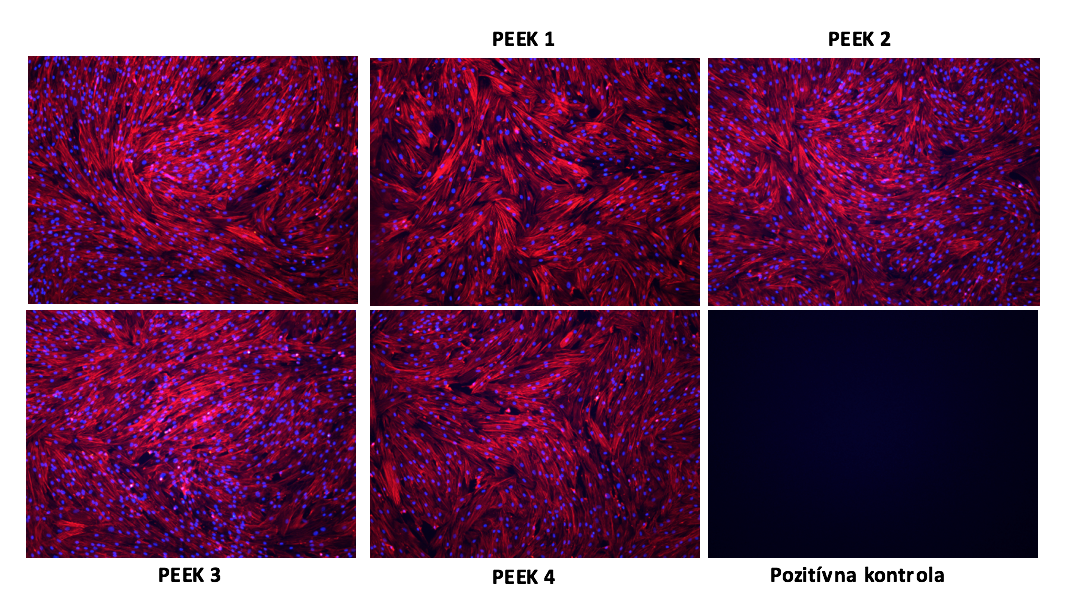

a) zapojenie sa do procesu návrhu vzoriek pre testovanie cytotoxicity

b) realizovanie testov cytotoxicity vzoriek z PEEK materiálov (filamenty na mezenchýmových stromálnych bunkách (toxický vplyv na morfológiu, cytoskolet, viabilitu a proliferáciu MSB in vitro)

c) riešenie úloh spojených s výberom testovacích metód a postupov, ktoré boli použité na experimentálne testovanie navrhnutých avyrobených vzoriek z materiálu PEEK ajeho derivátov

V roku 2017 boli takisto pripravené testovacie vzorky pre testy biokompatibility a viability buniek, ktoré boli v tomto roku aj zrealizované.

Obr. 4 Aditívne vyrobené vzorky z materiálu PEEK určené na laboratorne testovanie na humánnom bunkovom modeli v in vitro podmienkach